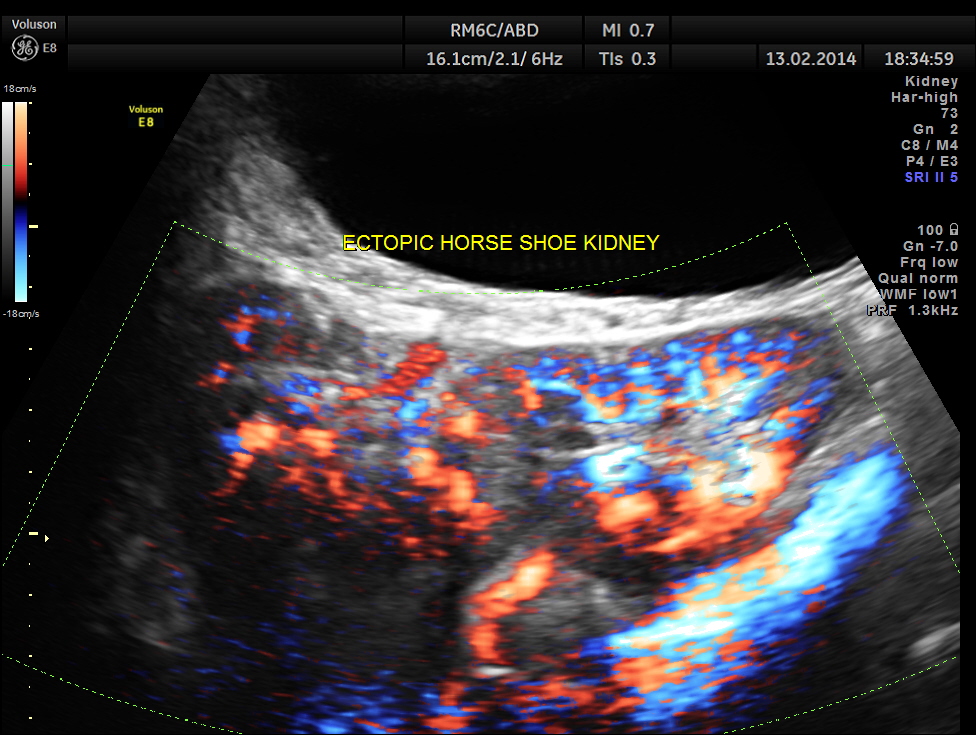

The following are the pictures of the kidney , which show the congenital horse shoe kidneys , placed ectopically in the pelvis. He had no urinary symptoms or low back ache at any time .

The power doppler pictures are given below.

Variant arterial supply Multiple, bilateral renal arteries Inferior mesenteric artery always crosses the isthmus Arteries arising from aorta or common iliac, internal iliac, external iliac or inferior mesenteric arteries